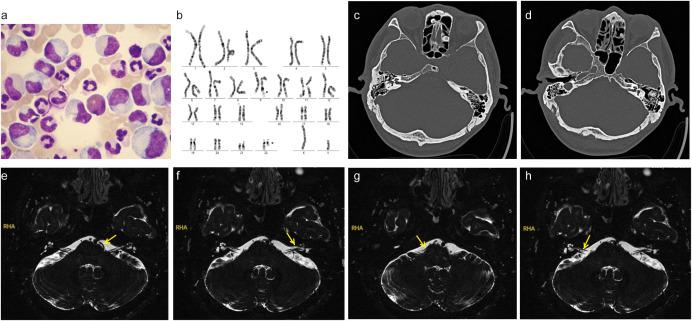

Chronic myeloid leukemia (CML) with sudden deafness as the first symptom is clinically rare and easily overlooked. No conventional treatment for CML-associated sudden hearing loss exists and hearing outcomes remain poor. Here, we describe a case in which sudden unilateral hearing loss was the first presenting symptom in a patient ultimately diagnosed with CML. The patient received imatinib mesylate, sodium bicarbonate, and allopurinol for CML, and systemic and local steroids, hemoreological therapy, and nutritional neurological drugs for hearing loss. Although the patient's CML was effectively controlled, his hearing could not be restored. In the second part of the manuscript, we present the results of a systematic review of case reports of CML-associated sudden hearing loss, identified by screening PubMed, Web of Science, and Medline. Seventeen patients were identified. Hyperviscosity syndrome and labyrinthine artery occlusive infarction were the most common pathogenic mechanisms of hearing loss. In terms of auditory outcomes, eight patients showed no improvement, while nine demonstrated positive outcomes. Among those with improved hearing, four had undergone cochlear implantation, one received intrathecal methotrexate, and one underwent leukoreduction therapy. Aggressive cochlear implantation could improve hearing outcomes in cases where cochlear ossification has not taken place and the leukemia is controlled.

以突发性耳聋为首发症状的慢性髓系白血病(CML)在临床上较为罕见,容易被忽视。目前尚无针对CML相关性突发性听力损失的常规治疗方法,听力预后仍然较差。在此,我们描述了一例患者,其最初表现为单侧突发性听力损失,最终被诊断为CML。该患者接受了甲磺酸伊马替尼、碳酸氢钠和别嘌醇治疗CML,以及全身性和局部性类固醇、血液学治疗和营养神经药物治疗听力损失。尽管患者的CML得到了有效控制,但其听力未能恢复。在本文的第二部分,我们展示了对通过筛选PubMed、科学网和Medline确定的CML相关性突发性听力损失病例报告的系统评价结果。共确定了17例患者。高黏滞血症和迷路动脉闭塞性梗死是听力损失最常见的致病机制。在听力结果方面,8例患者无改善,而9例显示出阳性结果。在听力改善的患者中,4例接受了人工耳蜗植入,1例接受了鞘内甲氨蝶呤治疗,1例接受了白细胞去除术。在未发生耳蜗骨化且白血病得到控制的情况下,积极的人工耳蜗植入可以改善听力结果。